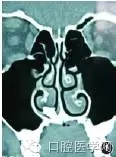

鼻竇CT(圖1)回報:高密度影像,懷疑鼻腔異位牙。

圖1 竇CT可見額外牙位于右側(cè)鼻腔